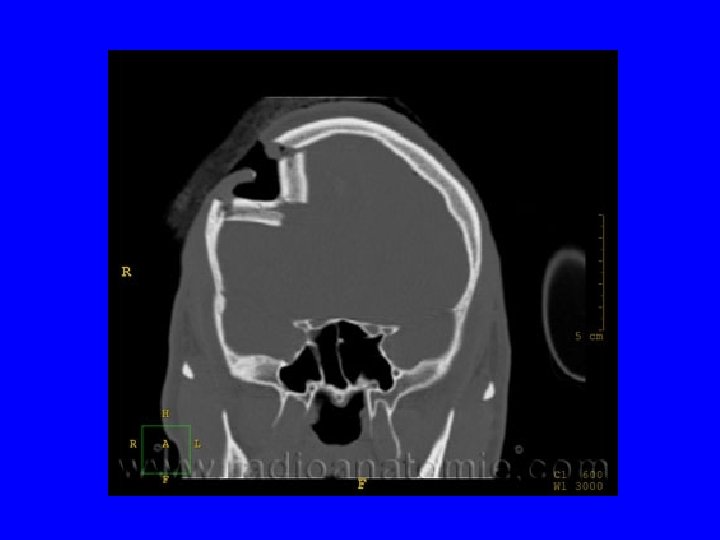

• • • D) Examens complémentaires Scanner cérébral Diagnostic lésionnel Suivi des lésions : Hémorragie méningée, intraventriculaire Hématome intra ou extra cérébraux Contusions Lésions axonales diffuses Œdème cérébral

IV. Conduite thérapeutique • Indications d’intervention neurochirurgicale en urgence après un TC – HED – HSDA – Hématome intracérébral avec effet de masse – Embarrure – Plaie crânio-cérébrale